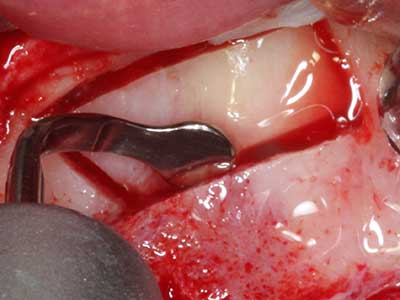

Si es preciso realizar intervenciones quirúrgicas en las que el hueso está en contacto directo con estructuras sensibles, como son los vasos sanguíneos o los nervios, los instrumentos rotativos presentan un enorme potencial de provocar lesiones iatrogénicas. Así, precisamente en la representación de nervios después de una lesión iatrogénica, o en el transcurso de la lateralización de un nervio para resecciones, reconstrucciones o incorporación de implantes, los equipos piezoeléctricos pueden resultar muy útiles para preparar la tapa ósea y retirar las partes de tejido duro cercanas al nervio (fig. 17-20). Por lo general, un ligero contacto del cordón nervioso con el inserto piezoeléctrico no tiene consecuencia alguna; ahora bien, un procedimiento poco cuidadoso con movimientos tipo sierra o piezas de trabajo sobre la base ósea aún existente puede provocar lesiones nerviosas temporales o incluso permanentes. Con todo, el riesgo de sufrir una lesión de este tipo se considera significativamente inferior que en los casos en los que se utilizan sierras y fresas (Pereira, Gealh et al. 2014).

Aplicación: Preparación cerca del nervio